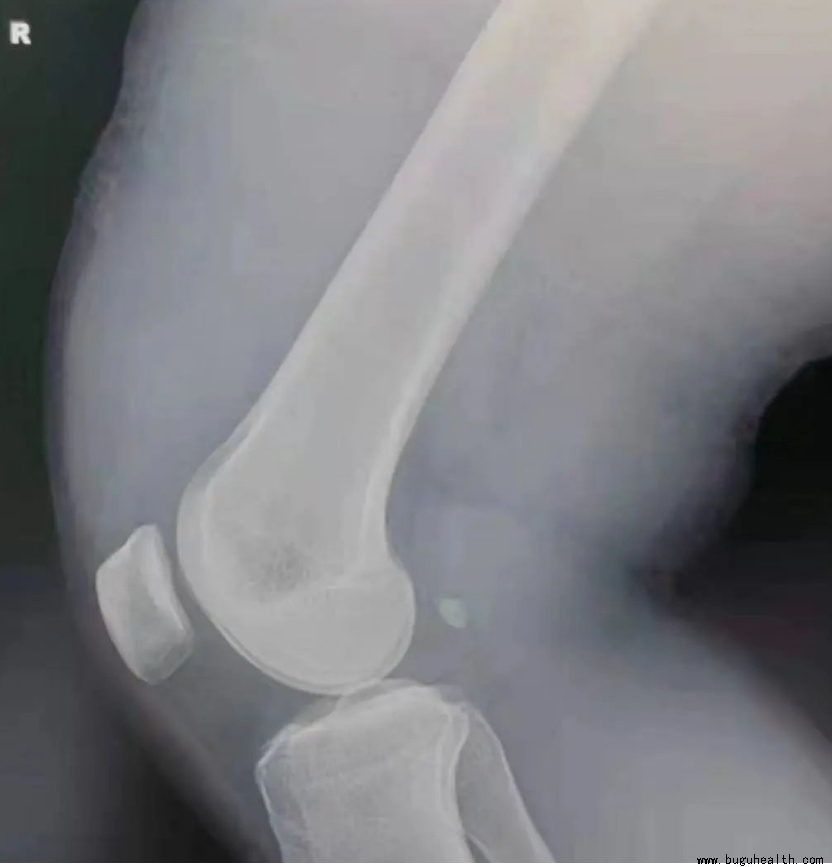

膝关节损伤在运动员中很常见,小到膝关节瘀青肿胀、软组织挫伤,大到需要长时间康复治疗的韧带损伤。实际上,超过了100种不同病理学因素可影响膝关节,很多膝关节损伤都需要进行外科手术并且需要进行长时间的康复和功能重建。

清除膝关节积液的重要性。膝关节的滑膜产生滑液,当膝关节发炎或者存在病变时,滑膜就会分泌更多的滑液,来试图清除炎症或者移除膝关节的异物,这样就产生了积液。当确诊膝关节积液增多是属于病理性渗出时,康复人员必须进行医学干预。如果存在膝关节积液,就一定要进行治疗。即使是不多的积液(20~30毫升)都会减少肌肉 50% ~ 60% 最大随意收缩能力,这种情况通常被称为“关节源性肌肉抑制”。此外,关节积液的小幅增加(如5毫升)也会增加膝关节内压,造成运动员的不适和焦虑。